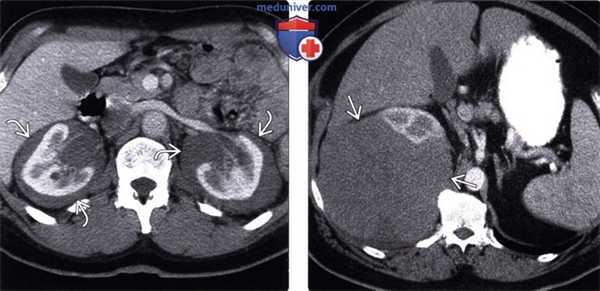

(Слева) КТ с контрастированием, аксиальная проекция: визуализирован двусторонний гидронефроз вследствие слившихся узловых метастазов забрюшинного пространства, ставших причиной мочеточниковой обструкции.

(Справа) КТ с контрастированием, аксиальная проекция: слившиеся узлы, окружающие чревный ствол, вследствие метастазирования рака пищевода. Рак дистального отдела пищевода часто метастазирует в верхние лимфатические узлы брюшной полости, печень или легкие.

(Слева) КТ с контрастированием, аксиальная проекция: гидроуретер и контрастируемое метастатическое поражение в левой поясничной мышце.

(Справа) КТ с контрастированием, аксиальная проекция: у Этого же пациента визуализирован контрастируемый метастаз, блокирующий левый мочеточник. Видны левая общая подвздошная артерия и вена, а также левая семенная вена. Для сравнения показан нормальный правый мочеточник.

(Слева) КТ с контрастированием, аксиальная проекция: у мужчины 21 года вследствие метастатической меланомы выявлены двусторонняя субкапсулярная гематома почки, паранефральные узелки мягкой ткани, забрюшинная лимфаденопатия и поражение мышц.

(Справа) В левой почке и околопочечном пространстве выявлена ФДГ-положительная опухоль, представляющая собой гематогенные метастазы меланомы в забрюшинное пространство. ПЭТ/КТ—идеальный метод визуализации ФДГ -положительных опухолей, так как часто позволяет обнаружить метастазы скрытых локализаций и в лимфатических узлах нормальных размеров.